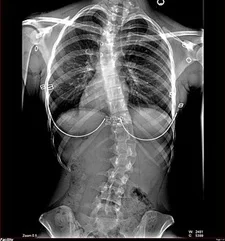

La escoliosis es una condición que se presenta en un gran número de personas alrededor del mundo. Se caracteriza por una curvatura anormal de la columna vertebral, lo que puede tener efectos negativos en la postura, la movilidad e incluso la función pulmonar en casos más graves. Afortunadamente, existen diversos tratamientos disponibles para abordar esta condición, y uno de los más comunes y efectivos es conocido como el Corsé de Boston. En el blog de hoyexplicaremos qué es el Corsé de Boston, cómo funciona y cuáles son sus beneficios en el tratamiento de la escoliosis.

El corsé de Boston es un tipo de ortesis específicamente diseñada para tratar la escoliosis. Es un dispositivo médico que se ajusta alrededor del torso del paciente y proporciona un soporte externo que ayuda a controlar y reducir la progresión de la curvatura de la columna vertebral.

El principal objetivo del corsé de Boston es aplicar una presión selectiva sobre la columna vertebral para corregir la curvatura anormal y mantener la alineación adecuada de la espalda. El corsé está hecho a medida y se ajusta individualmente a cada paciente, teniendo en cuenta la ubicación, la magnitud y el tipo de curva de escoliosis.